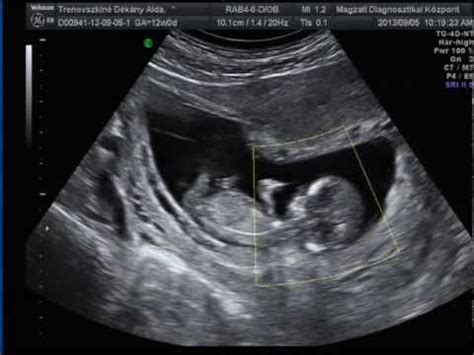

Az orvosok gyakran a magzat méretét veszik alapul, és határozzák meg, hogy hány hetes terhességnek felel meg az ultrahangon mért adat. Az ultrahang leleten feltüntetik, hogy a magzat adott napon, éppen hány hetes, napos magzat méretének felel meg.